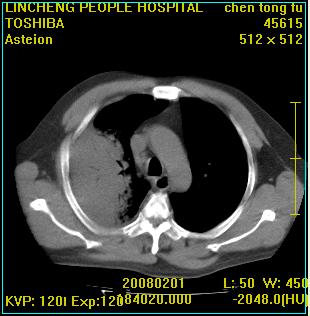

患者,男性,62岁。主因头晕,发热,咳嗽6天,高热达39度,esr19mm/h,wbc 3.9×10 9/l

大叶性肺炎并胸膜炎

右肺大叶性肺炎,胸腔积液。建议痰检。

实变区见空气支气管征,支气管通畅,考虑为大叶性肺炎,右侧少量胸水

1)考虑为:右肺感染性病变。建议:抗炎治疗复查。2)右侧少量胸腔积液。

考虑为右肺大叶性肺炎,胸腔积液,建议必要时纤维支气管镜检查,以排除肿瘤性病变。

右肺炎症并右侧胸腔少量积液。

大叶性肺炎并胸膜炎、胸水。

考虑为右肺大叶性肺炎伴少量胸腔积液,建议复查,如病变不吸收或吸收不明显,建议纤维支气管镜检查,除外细支气管肺泡癌的可能。

右侧大叶性肺炎,右侧少量胸腔积液.

实变区见空气支气管征,支气管通畅,考虑为大叶性肺炎,右侧少量胸水。